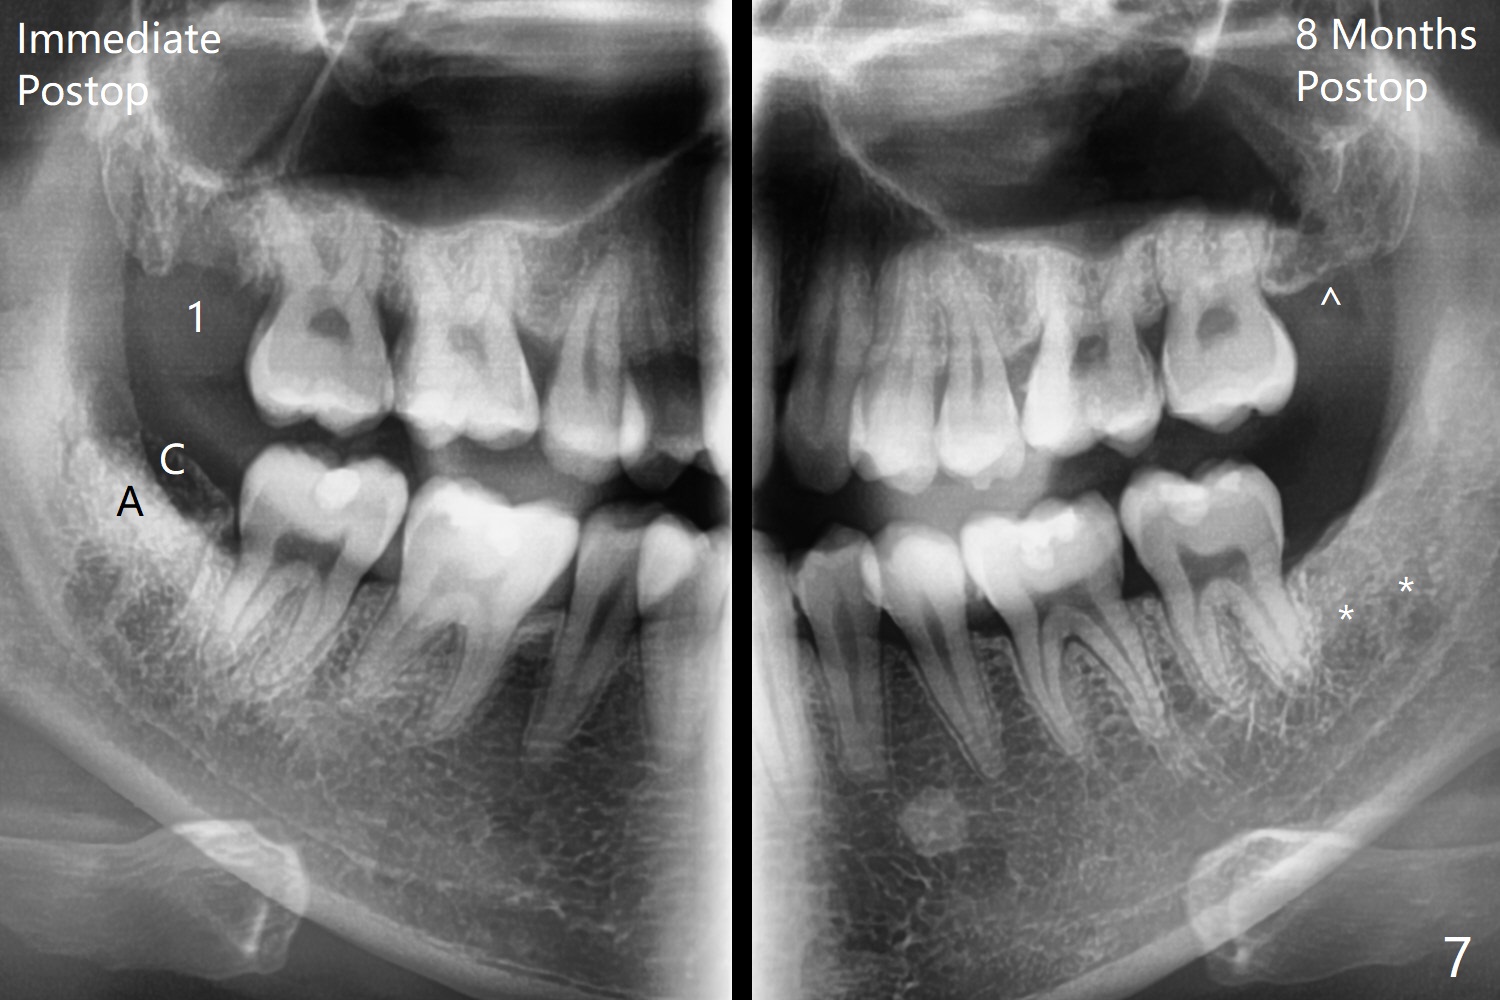

A 26-year-old man presents to clinic with pericoronitis at #17; the tooth #16 bites on the distal swollen gingiva of the tooth #17 (Fig.1). Since there appears to be no bone loss distal of #18, collagen plug, instead of Osteogen plug (Fig.2,3), will be placed in the socket(s) after extraction (Fig.4,5). For easy insertion, the plug is cut apically (Fig.6 *). The wound is closed with 4-0 plain gut suture. The patient returns for #1 and 32 extraction, eight months post #16 and 17 extraction. As usual, no bone substitute is placed in #1 socket after extraction (Fig.7). After #32 extraction, the distal socket looks large so that Augma (Bond Apatite) is placed and pressed (A), followed by a piece of Collagen Plug (C, to prevent Augma dissolved by saliva in case premature loss of suture). In fact there is also buccal defect at #32 due to chronic infection and heavy calculus. There is cortical bone formation at #16 socket opening (^). The mesial and distal sockets of #17 (*) seem to be obliterated because of placement of Collagen Plug. Return to Plug, Weichat Xin Wei, DDS, PhD, MS 1st edition 01/05/2019, last revision 09/22/2019